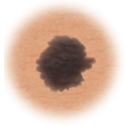

Melanoma

Asymmetry

When half of the mole does not match the other half

Border

When the borders (edges) of the mole are ragged or irregular

Color

When the color of the mole varies throughout

Diameter

If the mole's diameter is larger than a pencil's eraser

Evolving

Changes in the way the mole looks over time